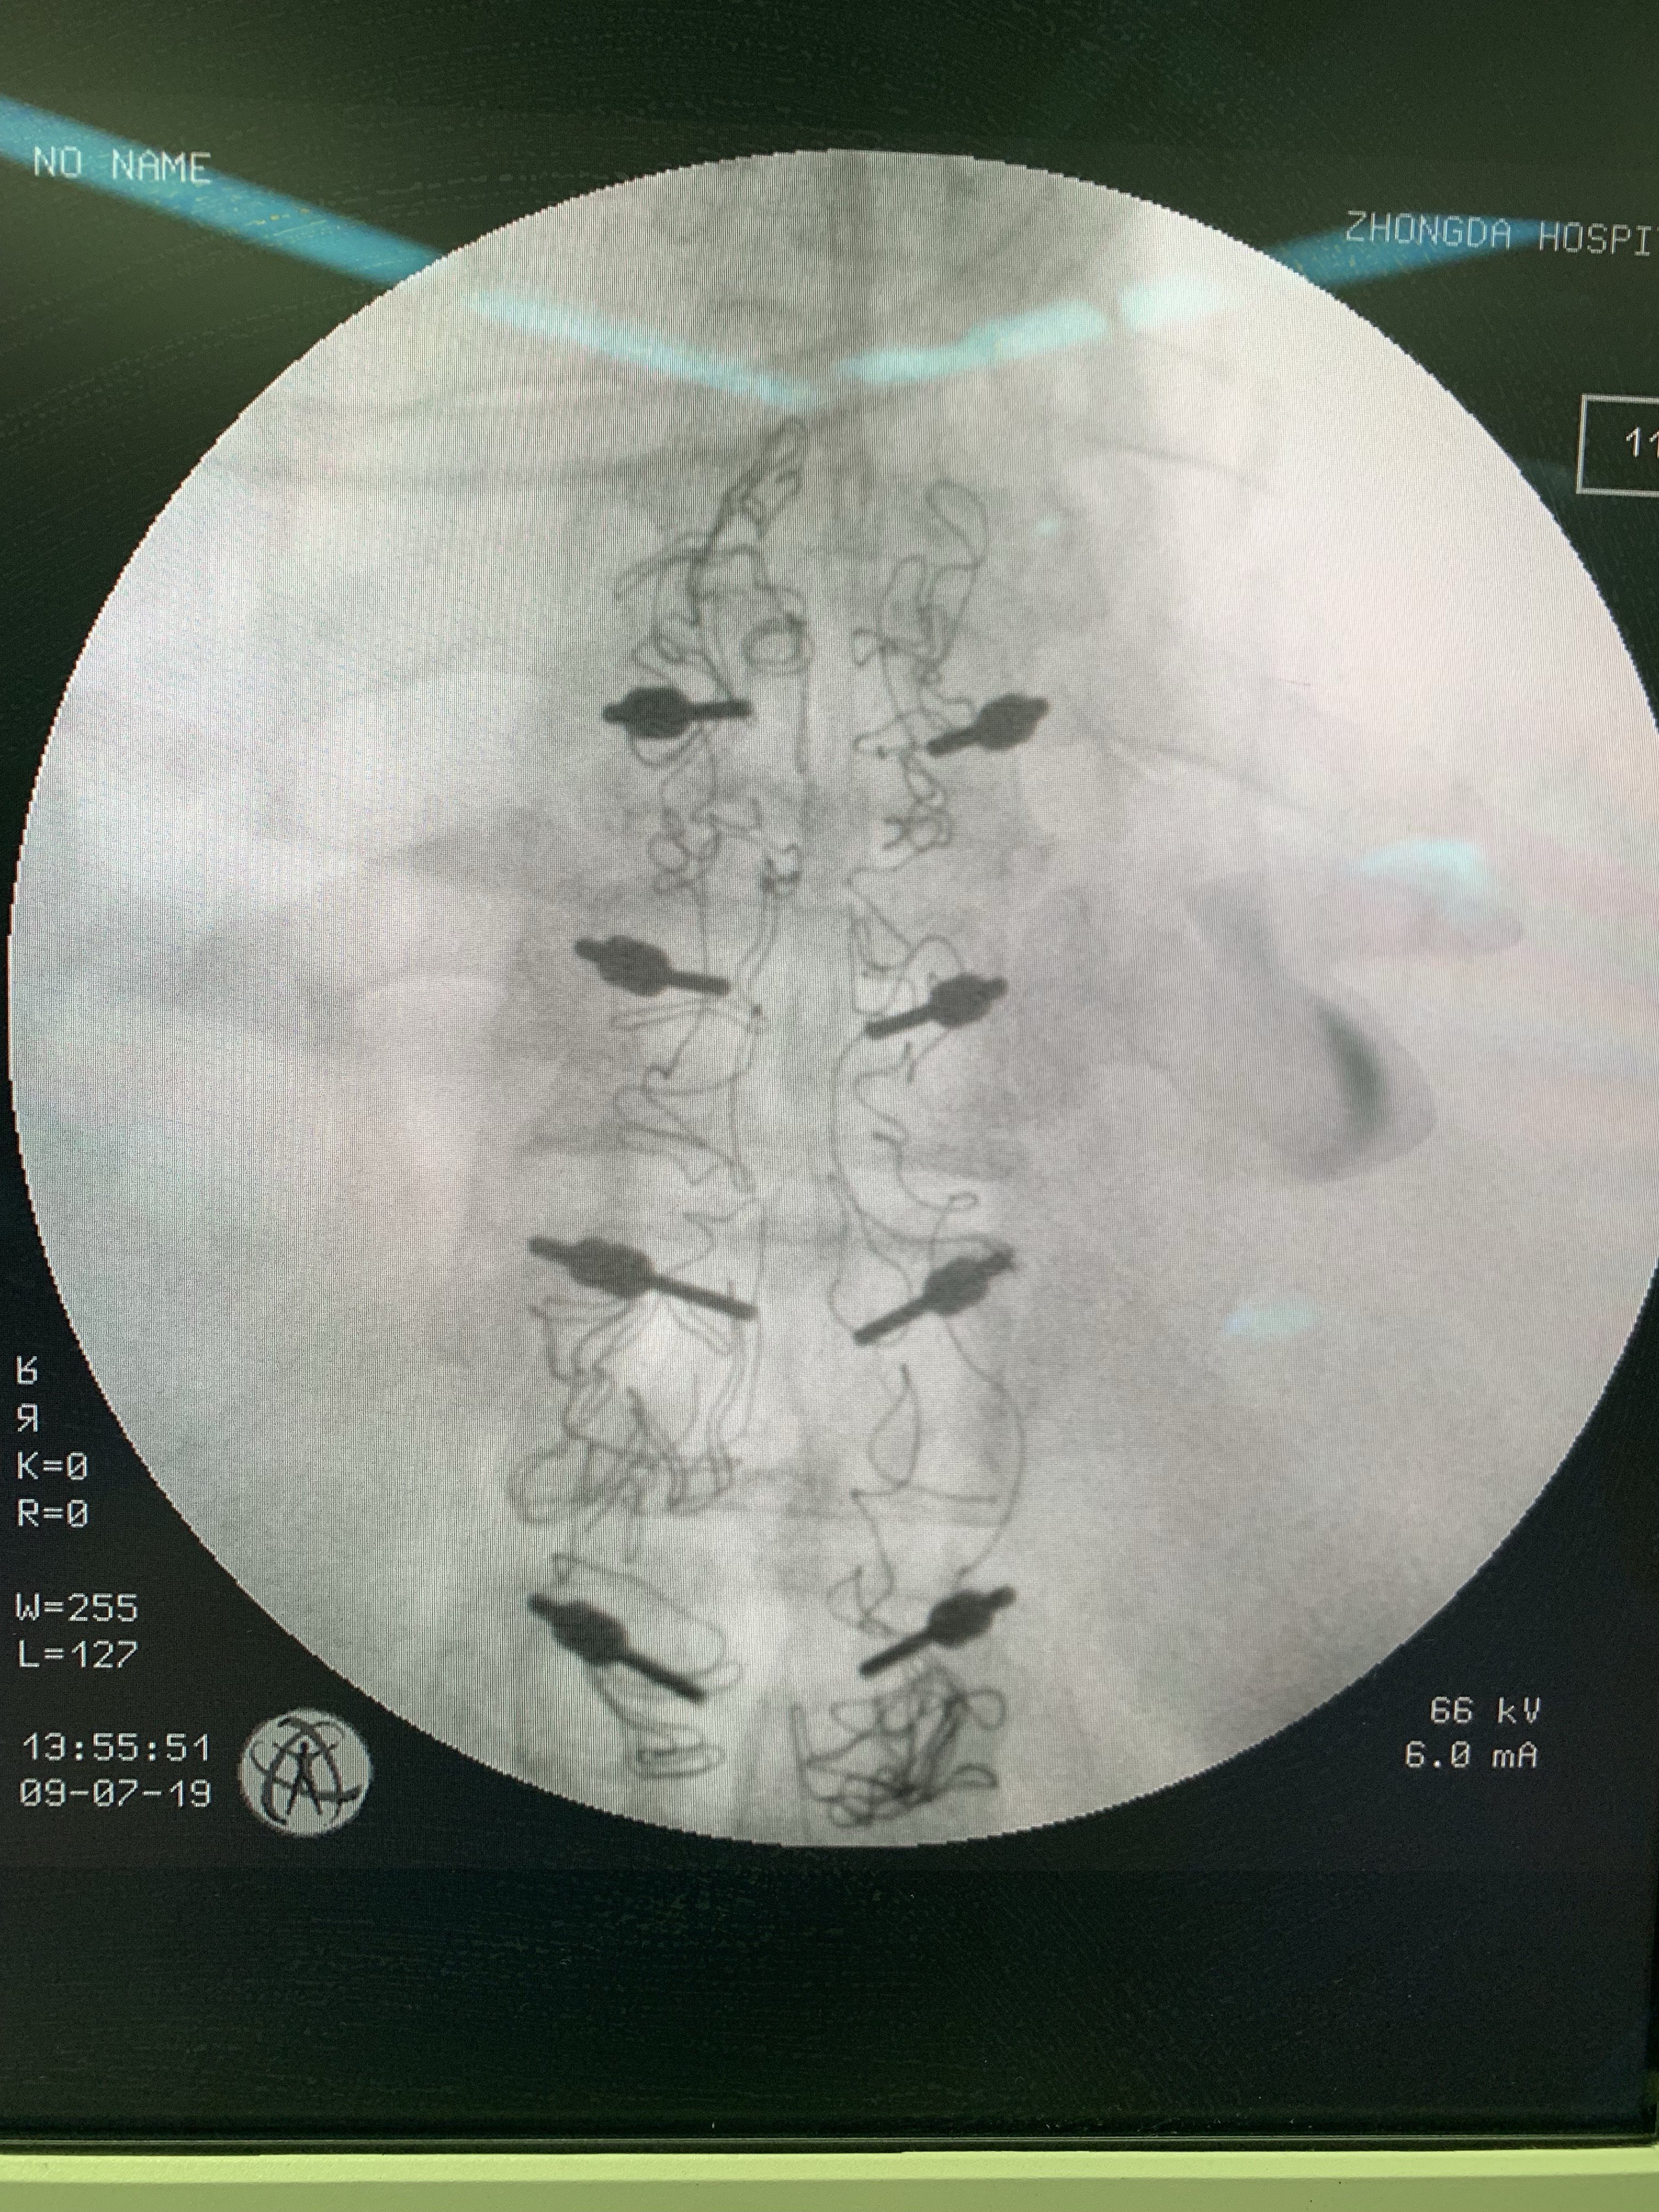

有限切口完成彻底减压

辅助有限椎弓根螺钉固定。